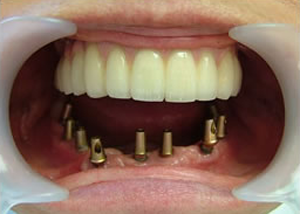

14.上は作った最終本物の歯が入っています。

下はチタンの土台が10本入りました。

15.下の土台は平行性あわせて削ったところです。